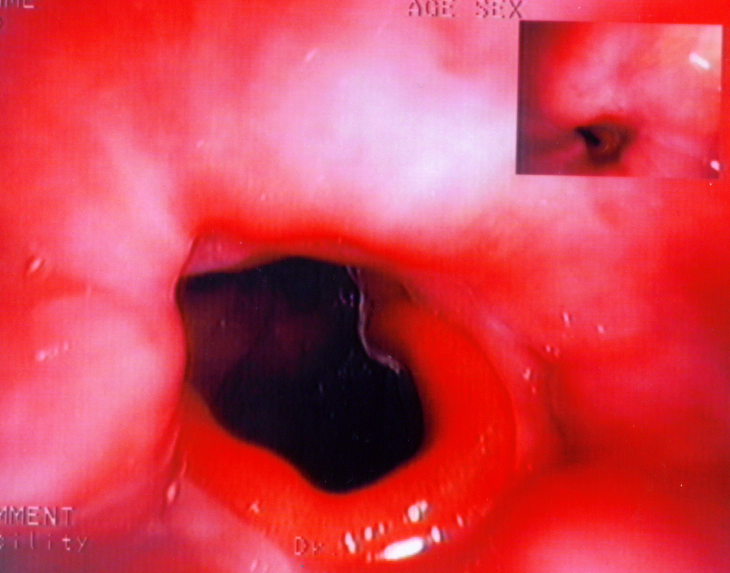

Endoscopic view of multiple gastric stromal tumors after suctioning of hemorrhagic products (Courtesy Dr. V. Penopoulos)